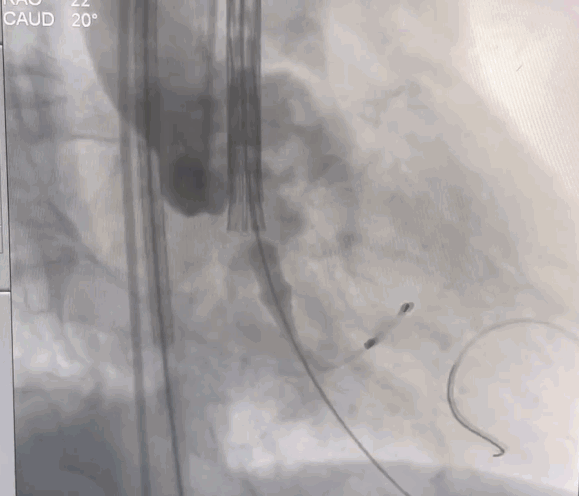

术中操作

经右侧颈动脉途径,直头导丝跨瓣成功后送入猪尾导管至左室,置入22F动脉鞘管。结合术前CT,装配好VitaFlow Liberty™27号瓣膜,在加硬导丝支撑下,送导管输送系统至主动脉根部并跨过主动脉瓣口,主动脉根部造影,确认瓣膜处于理想位置,在起搏下,经过慢释放、快释放及终释放,完成瓣膜释放过程。术后病人生命体征平稳,跨瓣压差明显改善,无瓣周漏。

球囊预扩